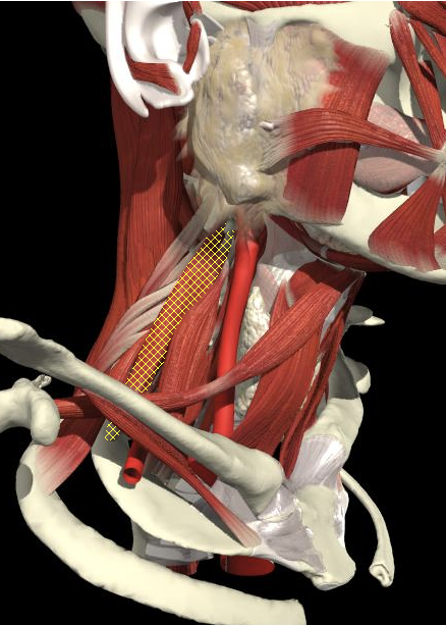

Structures to Avoid

Anatomy

Brachial Plexus

- From the intervertebral foramina, the 5 roots of the brachial plexus exit above the transverse processes of the corresponding cervical vertebrae and traverse through the interscalene groove before entering the floor of the posterior triangle of the neck.

- The upper, middle and lower trunks are enclosed within the interscalene fascial sheath as they emerge between the scalene muscles.

The Interscalene Groove

- The interscalene groove lies immediately behind the lateral border of the clavicular head of the sternocleidomastoid muscle at the level of the cricoid cartilage (C6)

- Approximately 1cm above the separation of the sternal and clavicular heads of the sternocleidomastoid muscle.

The BP lies inferior to a line from the posterior margin of the sternomastoid at the level of the cricoid cartilage to the midpoint of the clavicle

The BP lies inferior to a line from the posterior margin of the sternomastoid at the level of the cricoid cartilage to the midpoint of the clavicle. Scalenus medius is behind and above line.